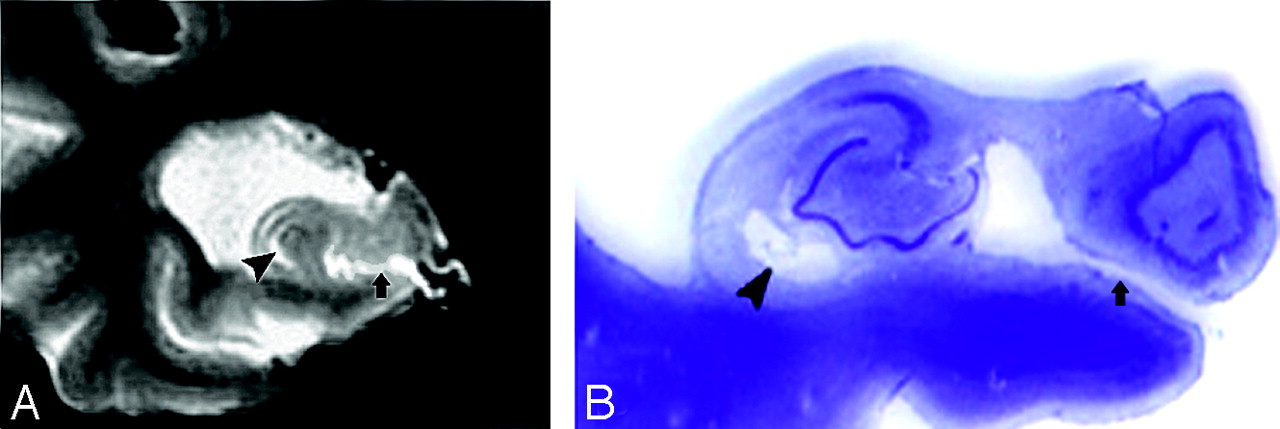

MR imaging appearance of hippocampal sulcus residual cavity (HSC).

A, The image was reformatted to a 1-mm-thick axial plane from the coronal T2 short-τ inversion recovery (STIR) scan, paralleling to the long axial of hippocampus (HSC, arrowheads; perihippocampal fissures [PHF], arrows).

B–D, Images were obtained by using the T2 STIR sequence (section thickness, 3 mm; HSC, arrowheads).

D, Region of interest of HSC (arrowhead).

On MR imaging, HSC appeared round, oval, or crescent, and the diameter ranges from 1 to 5 mm (Fig 1D). HSC were found with a prevalence of 64% in entire NC group and there was no significant difference between men and women (χ2(1) = 1.6; P > .05). The prevalence of HSC was 74% in AD compared with 75% in the age-matched NC group. In some cases, multiple cavities were present and appeared like a string of beads in both axial and coronal planes (Fig 1A, -C). In the NC subjects, 31% of the HSC were found in the hippocampal head, 50% were found in the hippocampal body, and 19% were found in the hippocampal tail. The observed prevalence of the HSC is found in Table 2.

In the coronal plane, the differentiation of a HSC in the presence of a dilated uncal sulcus is challenging. As seen in Figs 4A and 5A, these CSF structures look very similar. They can be differentiated by identifying the medial to lateral course of the uncal sulcus through its continuation with the ambient cistern. This relationship is clearly seen in a 3-year follow-up, when the uncal sulcus, but not the HSC, changed over time (Figs 4B and 5B). In the axial plane, the differentiation of a HSC from the PHF and from uncal sulcus can be difficult (Figs 6A and 7A). Comparing them, the HSC is again the more lateral and distributed along the vestigial primary hippocampal sulcus. We conclude that the coronal plane (Figs 6B and 7B) is most helpful for distinguishing between them.

A, Axial plane, arrowheads show the hippocampal sulcus residual cavity (HSC) and arrow shows the uncal sulcus. We can best differentiate them on the coronal plane.